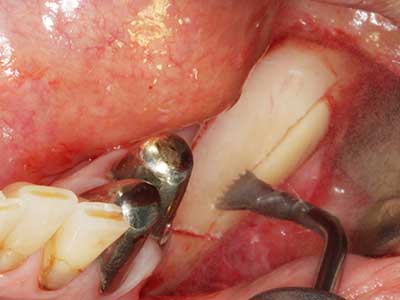

Sollen chirurgische Eingriffe mit unmittelbarer Knochenbeziehung an empfindlichen Strukturen wie Blutgefäßen oder Nerven erfolgen, so bergen rotierende Instrumente ein erhebliches Potential an iatrogener Schädigung. Gerade bei Nervdarstellungen nach iatrogener Schädigung, oder aber im Zuge einer Nervlateralisation für resektive und rekonstruktive Eingriffe oder Implantatinsertionen können piezoelektronische Geräte hilfreich sein Knochendeckel zu präparieren und nervnahe Hartgewebsanteile zu entfernen (Abb. 17-20). Ein leichter Kontakt des Nervstrangs zur Piezospitze bleibt dabei in der Regel folgenlos – allerdings kann eine unvorsichtige Vorgehensweise mit sägeartigen Bewegungen bzw. Ansätzen bei noch vorhandener knöcherner Unterlage durchaus temporäre oder aber auch permanente Nervschädigungen verursachen. Das Risiko einer solchen Schädigung wird jedoch als wesentliche geringer eingeschätzt als unter Anwendung von Säge- oder Fräsinstrumenten (Pereira, Gealh et al. 2014).